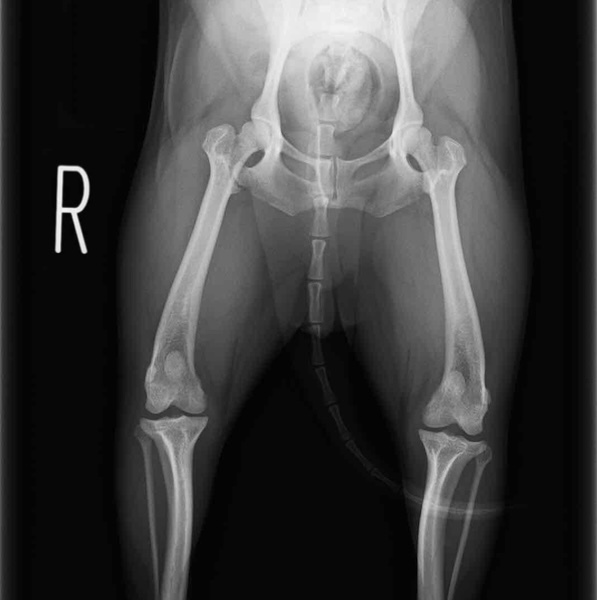

術前正面像

術後左後肢正面像

術前のTPAは左後肢33.1°右後肢26.8°でしたがTPLO実施により左後肢5.5°右後肢12°に矯正されました。